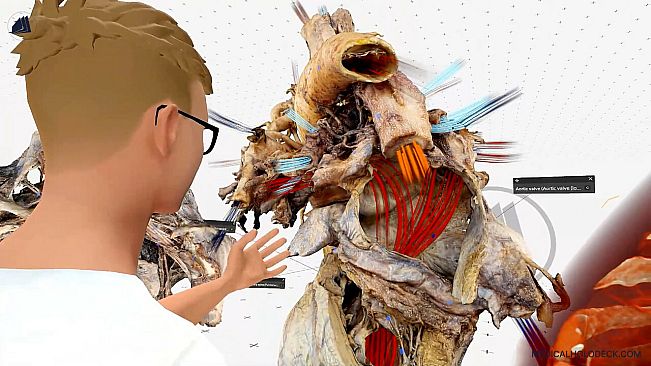

Experience medical education in virtual reality. Explore detailed 3D human dissections and 3D anatomy models. Automatically segment CT scans with AI, and exercise surgeries in an immersive environment.

Developed for future doctors, surgeons, nurses, and medical students, Medicalholodeck provides an immersive 3D environment to interact with patient data, medical imaging, high-res anatomical dissections, and anatomy models.

With advanced tools for surgical simulation, AI-powered segmentation, and anatomy study, you can visualize, manipulate, and collaborate on medical content and images.*

Explore human anatomy in full 3D, from any angle and scale. Examine pathologies in detail and deepen your medical understanding.

Dissection Master XR – VR-based human anatomy atlas and dissection lab, offering professional human dissections.